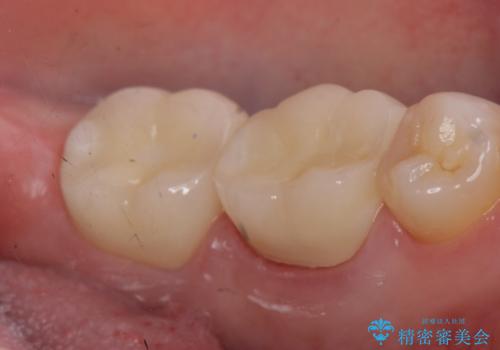

左下6、7番目の歯に根尖病変を認めたため、再根管治療後、オールセラミッククラウンによる補綴を行いました。

今回用いたオールセラミッククラウンは、ジルコニアフレームという白い素材の上にセラミックを盛っているため審美性が非常に高いのが特徴です。

またジルコニアは人工ダイヤモンドの材料にも使われているほど高い強度を持っており、そのためオールセラミッククラウンは審美性だけでなく、奥歯やブリッジの補綴も可能とするクラウンです。